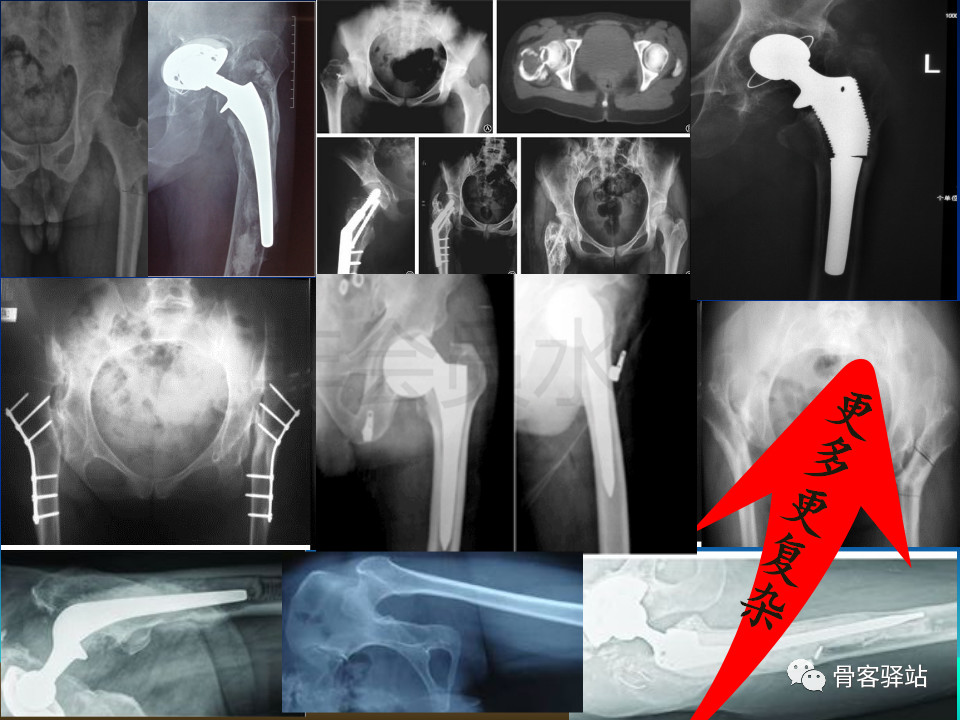

大转子延长截骨(eto)—股骨近端畸形髋重建必备技能

大转子延长截骨股骨近端畸形髋重建必备技能